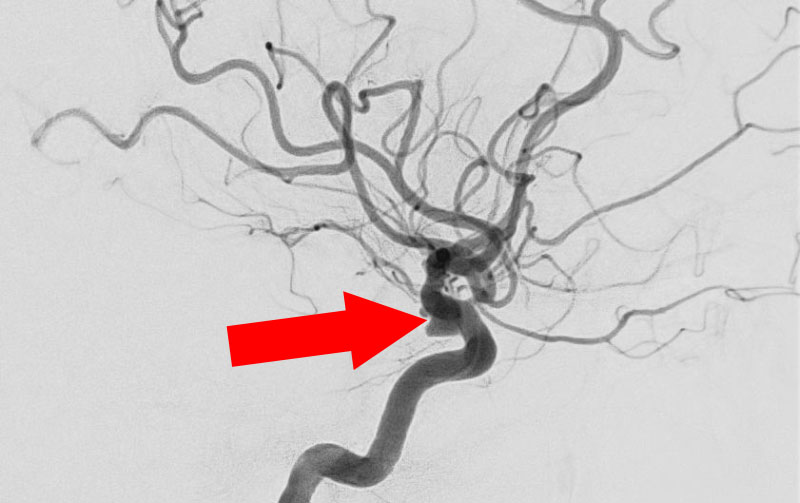

'26年4月

左内頚動脈脳動脈瘤

70代

大阪府の病院

No.1630 手術前